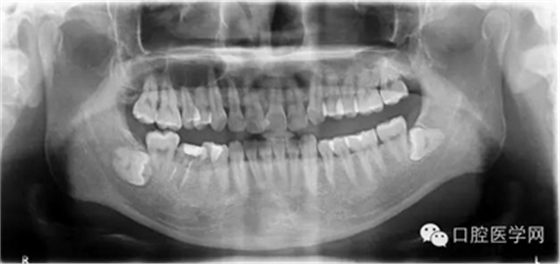

輔查:曲面斷層觀察齒c槽隔情況,為種植支抗植入熟悉解剖。

右上后牙段頰腭側各植入一枚種植支抗,以該骨性支抗為支撐,壓低伸長的右上后牙,從而為右下后牙的修復治療提供間隙。

在本例病例中,我們可以看到常規(guī)腭側植入直徑1.4長8mm的種植支抗,幾乎未鉆入骨皮質內,當然無法行使功能。 我們往往把治療的失敗歸咎于患者的不配合,實際上自己的操作規(guī)范也要回顧,如此才能發(fā)現(xiàn)問題,增廣經驗。 在本病例中,我們最終選取的支抗為12mm長,減去8mm的粘膜厚度,旋入骨皮質不足4mm,初始穩(wěn)定性佳!